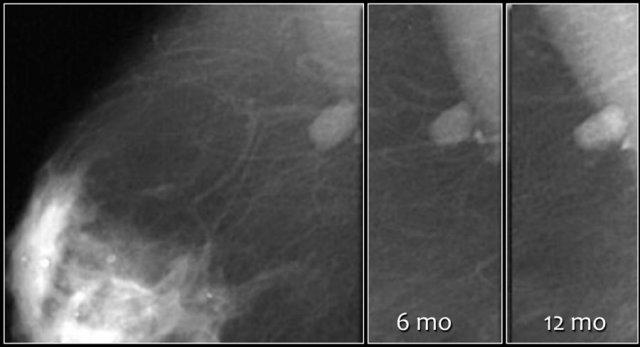

Hình ảnh phía trên cho thấy một vài vôi hóa vô định hình ban đầu được phân loại là BI-RADS 3.

Tại lần theo dõi 12 tháng, ghi nhận hơn năm vôi hóa trong một nhóm.

Tổn thương lúc này được phân loại là BI-RADS 4.

Kết quả giải phẫu bệnh là DCIS kèm ung thư xâm nhập.